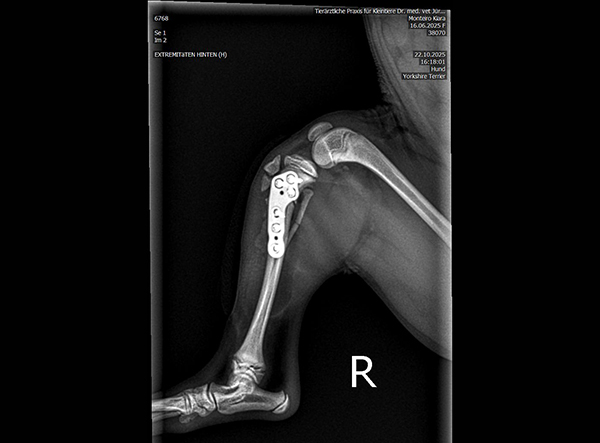

The patient, an 18-week-old female Yorkshire Terrier, was referred for surgery on October 21, 2025. The dog had sustained a fall from the owner’s arms, resulting in a fracture of the proximal tibial metaphysis just below the growth plate, along with a fibular fracture. Given the patient’s very small size and young age, precise anatomical fixation and minimal disruption of the growth zone were essential.

An open reduction and internal fixation (ORIF) was performed via a medial approach to the proximal tibia.Implant Used: 1.5 mm LeiLOX TPLO Swing Titanium Plate

- Micro-Precision Fit: Perfectly adapted to miniature canine bone anatomy.

- Stable Fixation: Maintains optimal alignment during bone healing.

- Growth-Friendly Design: Allows secure fixation without compromising nearby physes.

- Lightweight Titanium Construction: Minimizes implant load for young and active patients.

The surgery was completed without complications. Postoperative radiographs confirmed anatomical alignment and stable fixation. With careful rehabilitation, the young Yorkshire Terrier is expected to regain full function and resume normal activity pain-free.